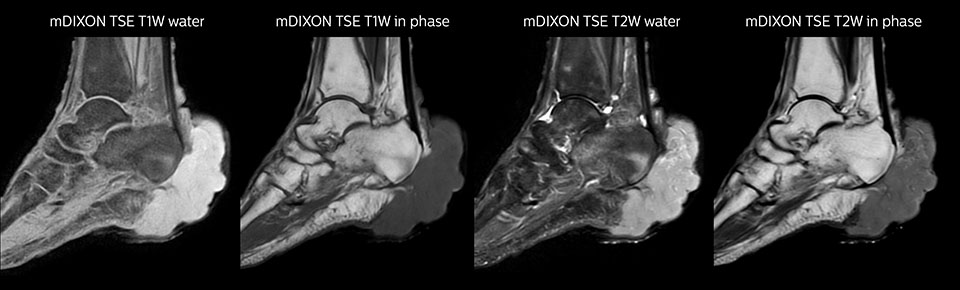

Auch im Allgemeinkrankenhaus Seirei Mikatahara in der Präfektur Shizuoka in Japan zeigt Prodiva 1.5T Wirkung. Der Radiologe Dr. Takahashi und seine Kollegen in der großen Radiologieabteilung arbeiten mit drei MR-Scannern, u.a. einem Ingenia 3.0T, für Untersuchungen einer Population mit vielen älteren Patienten. Als Ersatz für ein älteres MR-System entschied man sich für Prodiva 1.5T – und die klinischen Funktionen und Vorteile im Arbeitsablauf des neuesten Scanners haben große Wirkung gezeigt. Dr. Takahashi sagt: „Für ein 1.5T-System liefert Prodiva ausgezeichnete Qualität, die meine Erwartungen noch übertroffen hat. Inzwischen machen wir einige Untersuchungen, die wir vorher nur auf einem 3T-System ausgeführt hätten, mit Prodiva.“ Ein hohes Signal-Rausch-Verhältnis, Bewegungsunterdrückung und eine hervorragende Homogenität des Magnetfelds unterstützen ausgezeichnete Ergebnisse für das Team. „Ich bin besonders beeindruckt von der Qualität der Fettsuppression mit mDIXON XD, vor allem im Halsbereich und bei Gelenken der Extremitäten, die für uns häufig problematisch waren“, erläutert Dr. Takahashi. „Seit wir Prodiva haben, mussten wir aufgrund des hohen SNR, der Bewegungsunterdrückung und der hervorragenden Homogenität des Magnetfelds weniger Wiederholungsscans durchführen.“ Dr. Takahashi setzt Prodiva 1.5T für eine Vielzahl von Untersuchungen ein, u.a. Herz, Gefäße, Abdomen und muskuloskelettale Anwendungen. Darüber hinaus führt er auch Ganzkörperuntersuchungen mit T1, STIR, T2WI und Diffusionssequenzen auf dem Prodiva System durch. „Ich bin beeindruckt von der kurzen Vorbereitungszeit der Patienten und der schnellen Scandauer“, betont er. „Normalerweise ist die Diffusionsbildgebung des Körpers aufgrund von Verzerrungen sehr anspruchsvoll. Mit Prodiva erzielen wir hier sehr gute Ergebnisse.“